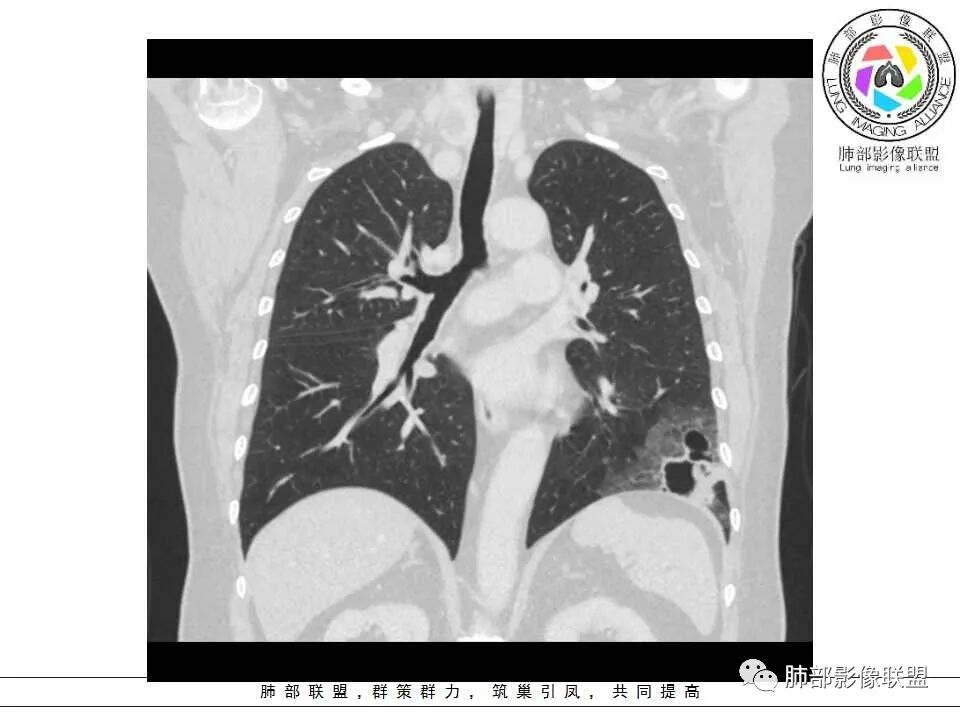

胸CT:左肺下叶囊腔,壁厚薄不均,可见壁结节,囊腔内可见断裂小梁,部分融合,周围边界较清楚GGO,胸膜牵拉,可见血管集束、支气管充气征,冠状位部分层面可见支气管在囊腔边缘截断。考虑:囊腔型腺Ca。鉴别:肺大疱感染,CPAM等。

病灶分两部分

周围大片GGO

中央囊实性病变

南边:

病史没提咳血,周围出血灶似乎不太好说

部分边界偏清

囊腔有张力,外形有分叶,壁厚薄不均,有间隔,有强化

1、左肺下叶外基底段不规则囊腔样病灶,囊腔内有条形影及血管穿行。

2、囊壁薄厚不均匀,稍显僵硬,有壁结节(对应边缘分叶等)、结节强化明显。

以上两条几乎将肺囊肿彻底排除在外,且高度怀疑新生物!

3、灶周环以大范围磨玻璃影,非常均匀,没有重力分布趋势,分叶状,边界隐约可变。

4、冠状位部分层面可见支气管在囊腔边缘截断。

囊腔型肺癌主要为腺癌,少数为鳞癌。

本例囊腔性病灶尽管腔壁稍显僵硬,壁结节凸显,但女性患者,灶周明显磨玻璃晕,都强烈提示为囊腔性腺癌。